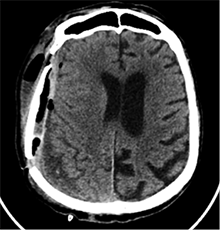

53 m. vyras sumuštas gatvėje ir greitosios medicinos pagalbos atvežtas į Priėmimo skyrių. Pacientui atlikta galvos kompiuterinė tomografija (GKT). Rasta: poūmė, stora, apie 16 mm dydžio subdurinė hematoma (SDH) dešinėje pusėje konveksitaliai ir ūmi nedidelė SDH kairėje pusėje frontoparietaliai. Vidurio struktūrų dislokacija (VSD) į kairę – minimali. Kairėje – kaukolės skliauto linijinis lūžis. Nustatyta nosies kaulų, nosies pertvaros, dešiniojo viršutinio žandikaulio kaktinės ataugos ir kūno, sinuso sienelių lūžių, dešinės akiduobės medialinio krašto lūžių ir dešiniojo skruostinio lanko lūžių (1 pav.). 2020 m. liepos mėn. pacientas skubos tvarka operuotas: atlikta dešinė kraniotomija, pašalinta hematoma. Atlikus kontrolinę GKT, buvo matyti, kad pašalinta didžioji hematomos dalis (2 pav.). Pacientas konsultuotas veido ir žandikaulio chirurgo, skubus chirurginis gydymas neindikuotas. Praėjus 3 savaitėms, pacientas, esant gerai funkcinei ir neurologinei būklei, tolesnio gydymo perkeltas į slaugos ligoninę, vėliau išleistas gydytis ambulatoriškai.

1 pav. Prieš pirmąją operaciją (poūmė, stambi, iki 16 mm SDH apie dešinįjį pusrutulį, ūmi nedidelė SDH kairėje F-P; VSD į kairę ~3 mm)

2 pav. Po pirmosios operacijos (didžioji hematomos dalis pašalinta, VSD be dislokacijos)